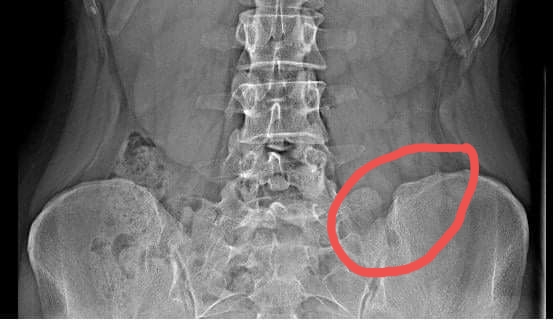

Čo znamená hrbolček na RTG panvy?

@lindusss2016 skúšala som ale nikto mi tam zatiaľ neodpovedal tak skúšam tu..no myslim len ten malý kopček na tej kosti panvovej

@lindusss2016 nemam...mam len dlhodobe bolesti v driekovej oblasti ale skor na pravej strane..toto je na lavej..len nahodou som si to vsimla ako taky hrbolcek na kosti alebo ako to mam povedat a samozrejme ma hned napadlo najhorsie..aj mne to pride rovnakej konzistenie ako zbytok kost len mi pride cudne ze to vytrca tak nad kost dost

@lindusss2016 na jednej strane je mi jasne ze nie vsetko je rovnake ale pozerala som si aj nejake ine snimky rtg a nevyzera mi to ako len nieco nepodstatne 🙈

@bbbbbbbbb jaj tak to mame asi podobne.Mna dost boli v kruzovej oblasti v drieku tam kde je chrbtica a hnavne v lavej strane.Raz pred 5 rokmi som bola na rengene drieku a tam som uz vtedy mala trochu platnicku pritlacenu.Potom to preslo a teraz 2 roky robim ako predavacka a posledne 4 mesiace to boli fakt.Ale pred asi 2t.som kychla a tak ma seklo.Pichli mi dake inekcie ale zeby nejako zabrali neviem.Ako aspon sa hybem a ohnem v pohode no ta bolest co je v drieku ostala.Aj v noci uz spim v polosede.Lebo ked lezim krize ma boli.A podla mna rengen mas ok len si asi trosku pootocena a preto to vizera ako hrbolcek